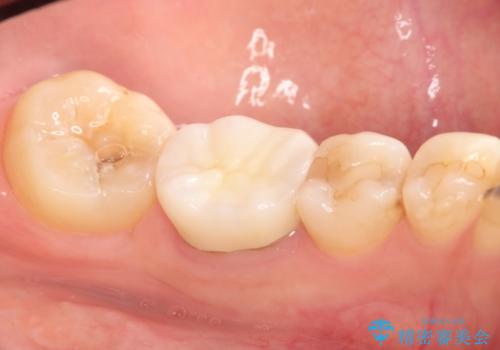

セラミッククラウンにて下顎の左右の歯にセラミッククラウンを装着する計画としました。

目立つところの銀歯がなくなり、審美的な改善ができました。